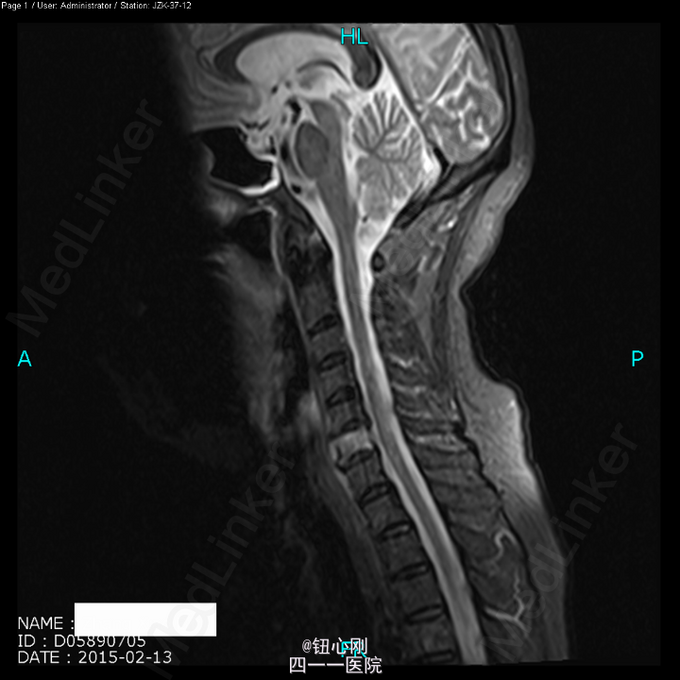

体检未见明显阳性体征。 辅助检查:血沉68mm/h,神经元特异性烯醇化酶23ug/l,余肿瘤指标正常。三大常规、肝肾功、电解质正常。 颈椎MRI、腰椎MRI及PET-CT扫描见图。

术前诊断:多椎体病变待查(转移瘤?) 诊断依据:老年女性,出现颈腰部疼痛,MRI及PET-CT扫描提示椎体多节段病变,以转移瘤可能性为大,同时血沉升高。 处理:2015-03-31在全麻下行颈6椎体病变前路次全切+钢板钛网植骨融合内固定术。术中所见:颈6椎体骨质疏松,部分硬化,未见鱼肉样组织。术后切除骨质送病理检查。 病理报告:骨小梁稀疏,其间有纤维组织,同时可见硬化死骨。 术后诊断:颈6椎体骨质疏松性骨坏死。

随着医学影像学及脊柱微创手术的发展,骨质疏松性椎体骨坏死逐渐被认识。该病临床上并非少见,骨坏死会导致椎体逐渐塌陷与进行性后凸畸形,引起患者长期腰背痛,甚至出现脊髓神经受压而瘫痪。患者为老年,主诉脊柱疼痛,MRI有椎体信号改变,因而易与脊柱转移性肿瘤混淆。骨坏死椎体在T1WI加权像上呈界限清楚的低信号区域,在T2WI加权像及脂肪抑制序列像上呈界限清晰高信号区域。这是与脊柱转移性肿瘤相鉴别的要点,对于累计整个椎体的骨坏死更需注意鉴别。 如疼痛不缓解或发生后凸畸形,可行椎体后凸成形术。